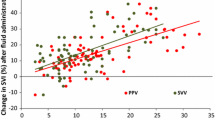

Hemodynamic variables at the study baseline, during the ARM, before the fluid challenge and after the fluid challenge between responders and non-responders are shown in Table 2. ∆PVP during an ARM predicts FR with an area under the ROC curves of 0.76 (95% CI, 0.63 to 0.86). The optimal threshold was a ∆PVP value of 5 mmHg (95% CI, 4 to 6) with a sensitivity of 66% (95% CI, 47 to 81) and a specificity of 82% (95% CI, 63 to 94) (Fig. 2). Proportions of values lying in the grey zone (value presenting a sensitivity lower than 90% or a specificity lower than 90%) ranged from 43 to 67% according to the tested variable (Table 2). The AUC’s for predicting FR were not different between ΔPVP and other hemodynamic variables such as ΔCVP and PPV (Table 2; Supplemental Fig. 1).

Receiver operating curves generated for changes in stroke volume index (SVI) induced by alveolar recruitment maneuver (ARM), changes in peripheral venous pressure induced by ARM, showing the ability to predict the effect of a volume expansion. Notes: alveolar recruitment maneuver consisted of applying a continuous positive airway pressure of 30 cm H2O for 30 s. The grey zone shows is delimited by two cut off values corresponding to a sensitivity of 90% (upper right corner) and a specificity of 90% (lower left corner). Values lying in the grey zone express a degree of uncertainty wherein the physician should pursue a diagnosis using additional tools. Legend: AUC: Area Under the Curve